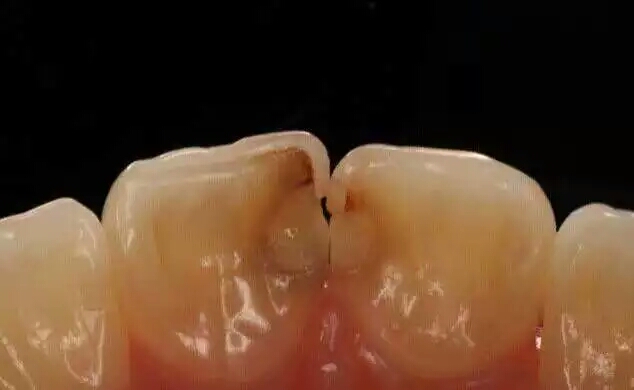

虽然导致口臭的原因有肠胃因素,但你可知道口腔疾病照样也会让你产生口臭?尤其是当你的牙齿发生蛀牙时,你的口腔里就像有了一个大型的垃圾场,无时无刻的散发着那股醉人的味道。

虽然蛀牙是由细菌为主的多种因素导致的,但究其根本就是你的口腔卫生差!一旦你没有做好口腔清洁卫生工作,饭后不及时刷牙,导致食物残渣残留,那么牙齿就会慢慢发生龋坏,牙洞里面就会有很多的细菌不断破坏牙齿,残渣也会慢慢的塞嵌进入蛀洞内。这些食物残渣在细菌和微生物的作用下,慢慢腐化发酵,从而产生一股难闻的气味!你说你口臭怪谁呢?

简单原理就是:食物残渣——繁殖细菌(产生酸性物质)——破坏牙釉质(牙釉质脱落)——牙本质露出(牙本质叫疏松更易破坏)——形成龋洞(由小到大)举个栗子:牙齿与骨的成份类似,也有钙盐和蛋白质。做酥鱼多放醋,烧很长时间连骨头都酥了,原理就是脱钙,只剩下骨蛋白。同样道理,牙缝中的酸性物质也可以腐蚀牙齿。当然,这种腐蚀是需要时间的。

浅龋:细菌只附在牙釉质层,初期表现为牙釉质面上有褐色或黑褐色的斑块,一般无症状,在检查时下被发现。

中龋:细菌已经攻到牙本质层了,这种情况下,有可能一开始会感觉到酸痛,但是过一段时间就慢慢没那么明显了。 深龋:细菌攻破牙本质快接近牙髓的时候,就比较严重了,一般遇到冷热酸甜都是很酸痛或刺痛。严重的还会扩散到牙周,引发牙周感染。